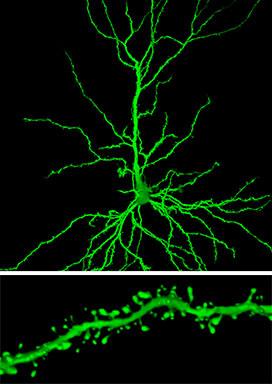

When researchers looked at certain neurons (similar to the one shown on top) in rats treated with riluzole, they found an important change in one brain region, the hippocampus: more clusters of so-called spines, receiving connections that extend from the branches of a neuron (bottom).

Credit Dr. John H. Morrison's lab, The Icahn School of Medicine at Mount Sinai